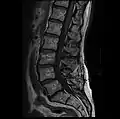

MRI lumbar spine with degeneration, post-hemilaminectomy L4-5 (sagittal T2 FRFSE)